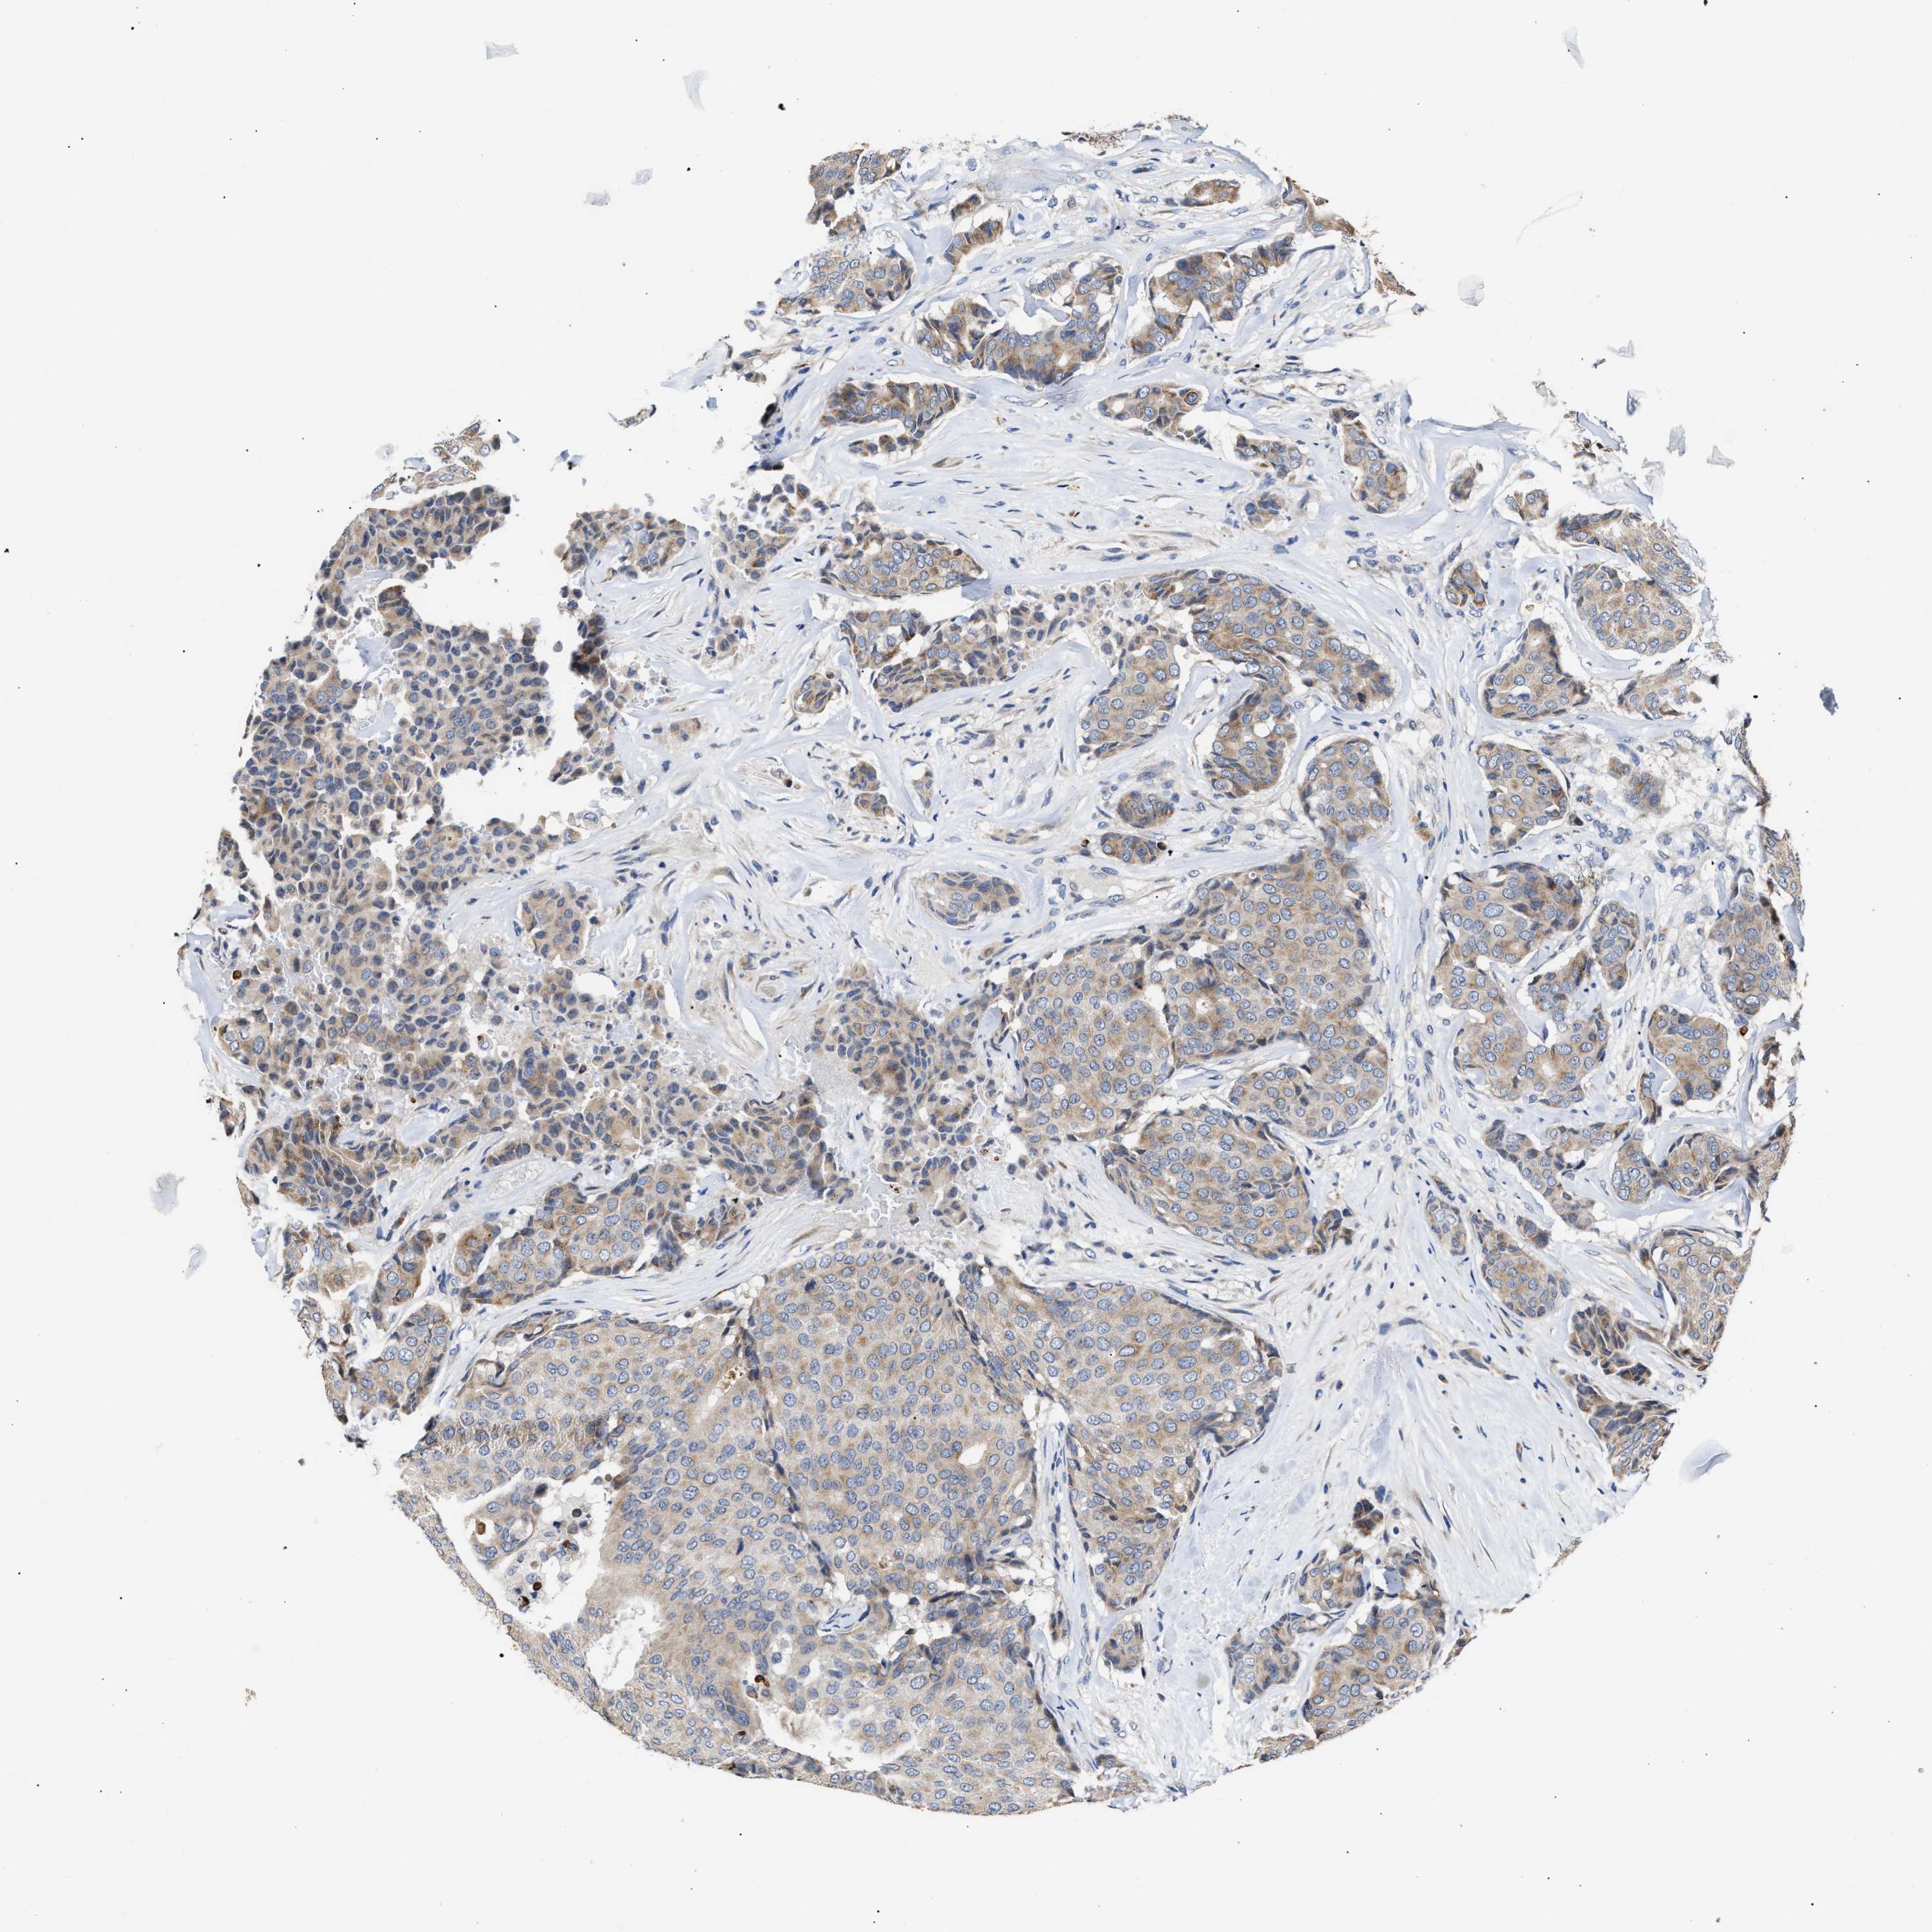

CANCER BREAST CANCER Show tissue menu

BRCA TCGA BRCA VALIDATION PROTEIN EXPRESSION

ANTIBODIES

AND

VALIDATION